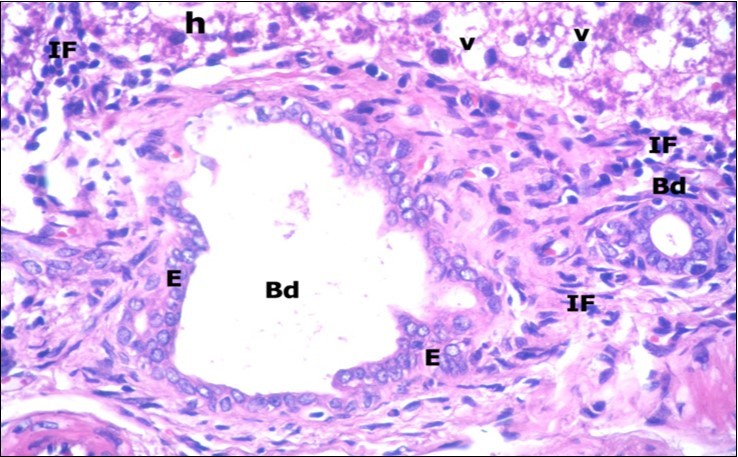

Examination of H&E stained sections of the 1st group (control group) revealed hepatic architecture of tightly packed cords of hepatocyte with vesicular nuclei and acidophilic cytoplasm radiating from the central vein (Figure 1). Portal area was composed of a portal vein, branch of hepatic artery and bile duct lined by single cuboidal cells with dark rounded nuclei. Blood sinusoids with their endothelial lining of Kuppfer cells were noticed in between hepatic cords (Figure 2). Examination of the liver sections of the 2nd group (vitamin E treated group) showed nearly the same histological features as the 1st group. The 3rd group (ZnONPs-treated group) showed a marked loss of the normal liver arrangement with dilated congested central veins and blood sinusoids. Most of hepatocytes had large cytoplasmic vacuoles and darkly stained nuclei other hepatocytes were ballooned (Figure 3). The portal area showed dilated congested portal vein with proliferation of bile duct, necrotic foci in between the hepatocytes with inflammatory cellular infiltration (Figure 4). The portal area showed also elongation of the endothelial lining of dilated congested portal vein and increasing amount of connective tissue fibers (Figure 5). There was congested hepatic artery with increasing thickness of its muscular layer (Figure 6). Bile duct showed proliferation with stratification of its epithelial lining (Figure 7).

Figure 7.A photomicrograph of a section in the liver of ZnONPs-treated adult albino rat showing proliferation of bile duct (Bd) with stratification of its epithelial lining (E). Mononuclear cellular infiltration (IF) in the portal area and hepatocytes with darkly-stained nuclei (h) and vacuolated cytoplasm (v) are also seen. (H&E X400)